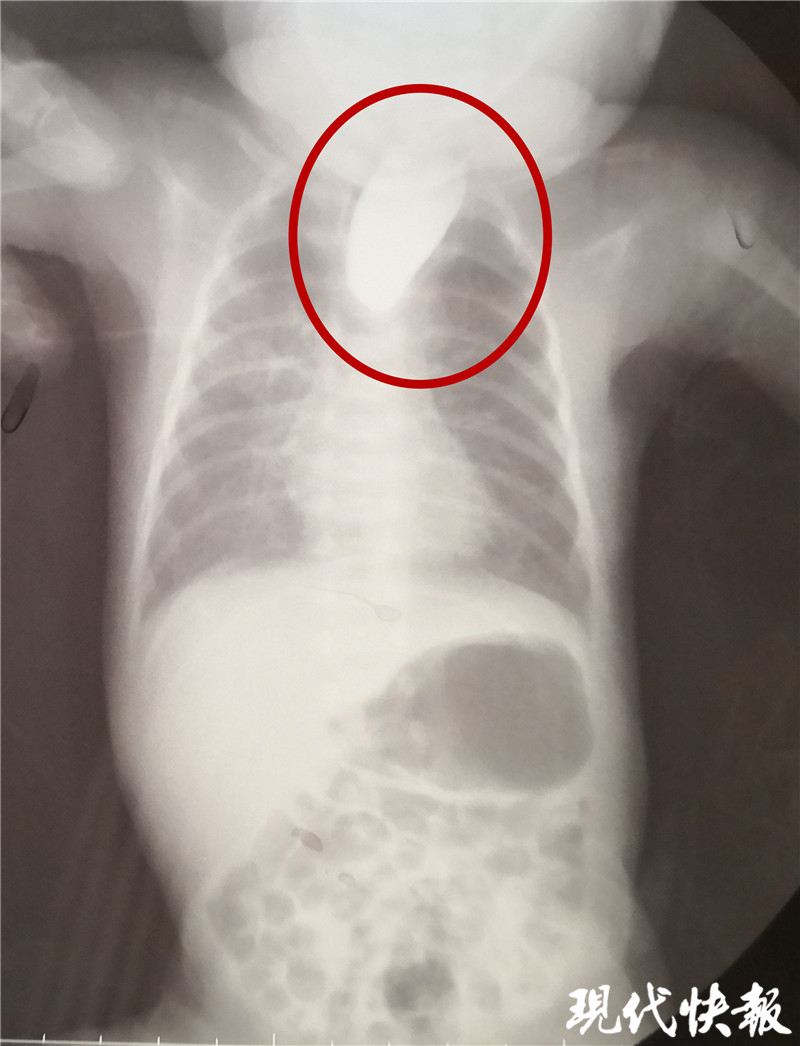

△食道閉鎖

現(xiàn)代快報(bào)記者了解到,9月8日,東東從當(dāng)?shù)蒯t(yī)院轉(zhuǎn)入淮安市婦幼保健院治療,檢查顯示東東的食道是個“死胡同”,明確診斷為食道閉鎖。“從片子上看,這個白色的造影劑到了食管上端就無法向下流了,說明孩子的食管上端是不通的、閉塞的。同時,孩子腸腔里面有氣體,這個氣體是通過氣道到食管的遠(yuǎn)端,到達(dá)胃和腸道內(nèi)。”淮安市婦幼保健院小兒外科副主任醫(yī)師夏順林說,這個寶寶如果不及時手術(shù),就會面臨兩個問題,一個就是唾液咽不下去,會嗆入肺部形成吸入性肺炎,同時胃和食管遠(yuǎn)端與氣管相通,胃內(nèi)的胃酸容易反流到氣道里面,進(jìn)入肺部形成化學(xué)性肺炎。